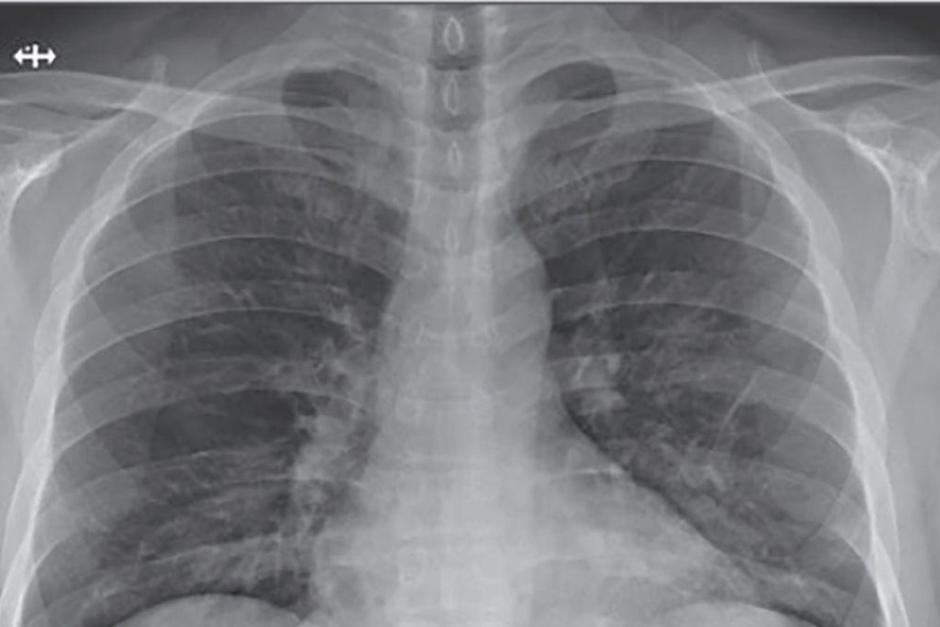

Se puede ver que los pulmones sanos tienen una gran parte de color negro, esto es aire. En los órganos de personas fumadoras se aprecian líneas blancas que indican cicatrización y congestión y en las de una persona que padeció Covid-19 el color que predomina es blanco.

COVID LUNGS

Texas doctor @BKendallMD tells me “post-COVID” lungs are worse than any smokers lungs she has ever seen. And it’s a trend she is witnessing in current and recovered patients. Our story tonight on @NewsNationNow.

Scroll: 1) Healthy 2) Smokers 3) COVID pic.twitter.com/Iu9V8OrpnK